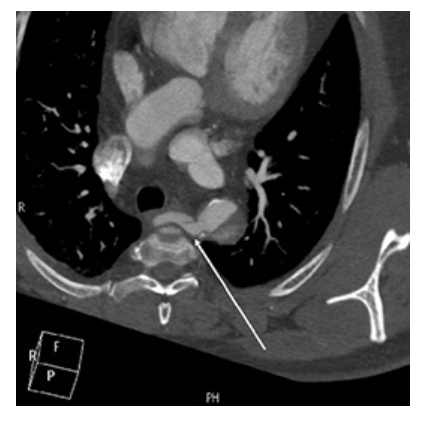

Aberrant Right Subclavian Artery. Axial contrast-enhanced CT shows aberrant right subclavian artery moving toward the right arm crossing the midline of the body (arrow).